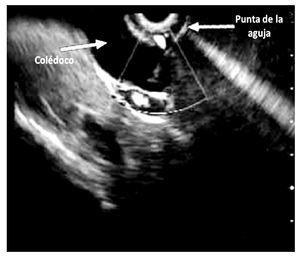

¿ Figura 1. Colédoco dilatado por cáncer de páncreas, puncionado bajo USE.

¿ Figura 4. Colédoco dilatado por cáncer de páncreas, sin flujo al dopler A). Punción del colédoco B). Colangiograma C). Paso de la prótesis transduodenal D). Drenaje biliar con total pasage de prótesis transduodenal E). Visión endoscópica de prótesis F).